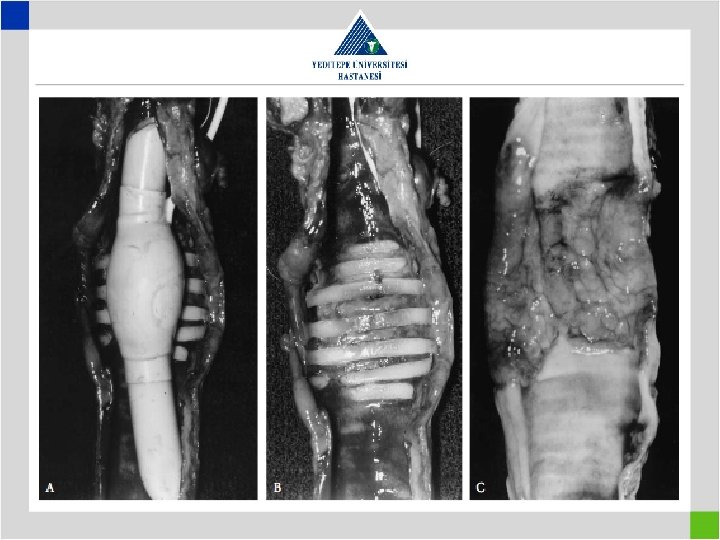

Laryngotracheal Resection with Posterior Membrane • Especially postintubation stenosis involves cricoid cartillage 360° • The scar tissue on the posterior cricoid plate needs to be excised